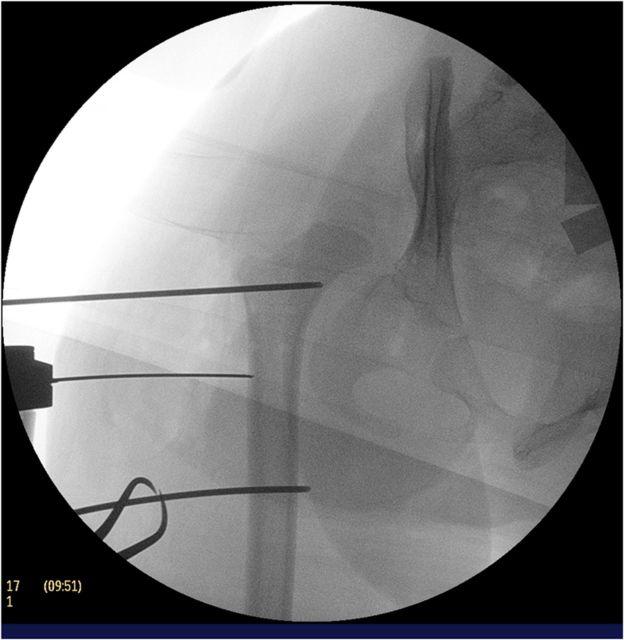

A combined procedure including open reduction, femoral shortening osteotomy, and an acetabular procedure is often necessary to obtain a desirable result in children of walking age who have a high-riding hip dislocation.

STEP 4 FIRST FEMORAL OSTEOTOMY: Expose the proximal part of the femur subperiosteally and make necessary markers for determining the amount of shortening and rotation at the time of osteotomy.

STEP 5 HIP JOINT STABILITY: Check femoral head reduction stability with the proximal end of the osteotomized femur.

STEP 6 FEMORAL SHORTENING: Decide the amount of shortening and rotation for the best femoral head reduction.

步骤4 首次股骨截骨:骨膜下暴露股骨近端,在截骨时做出必要的标记,以确定缩短和旋转的量。

步骤5 髋关节稳定性:用截骨股骨的近端检查股骨头复位的稳定性。

步骤6 股骨缩短:确定最佳股骨头复位所需的缩短和旋转量。